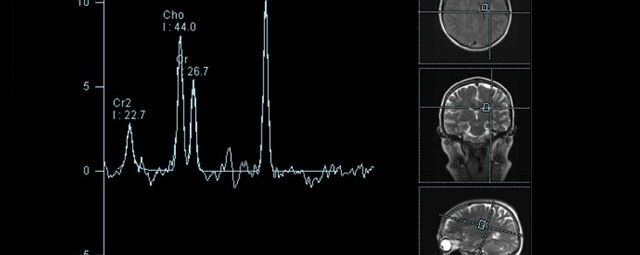

• Tumore, ggf. mit Spektroskopie

Spezialtechniken der Magnetresonanz

• Diffusionswichtung

• Perfusionswichtung

• Suszeptibilitätswichtung

• MR-Spektroskopie

Diese Verfahren werden bei verschiedenen Fragestellungen in verschiedenen Körperregionen in die Messprotokolle sinnvoll eingefügt. Teilweise können dadurch Differenzierungenverschiedener krankhafter Prozesse verbessert werden.